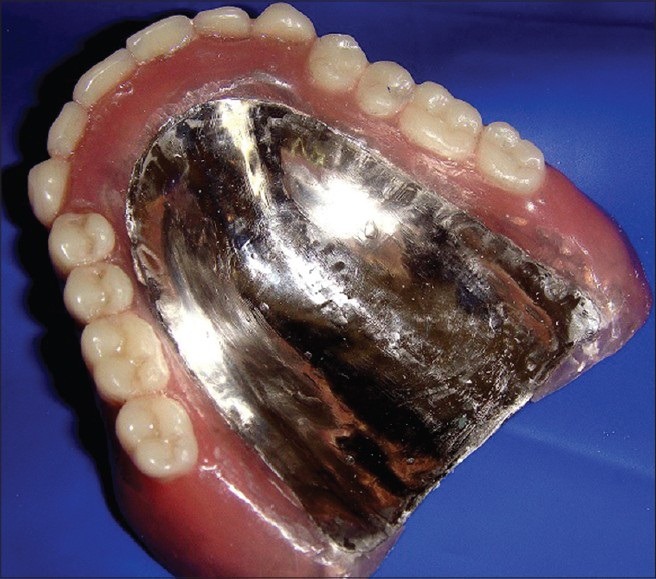

Materials:

- Acrylic: The base of the denture is usually made of acrylic material, which can be tinted to resemble gum tissue.

- Porcelain or Acrylic Teeth: The artificial teeth on the denture can be made from porcelain or acrylic. Porcelain teeth are more wear-resistant and have a more natural appearance.